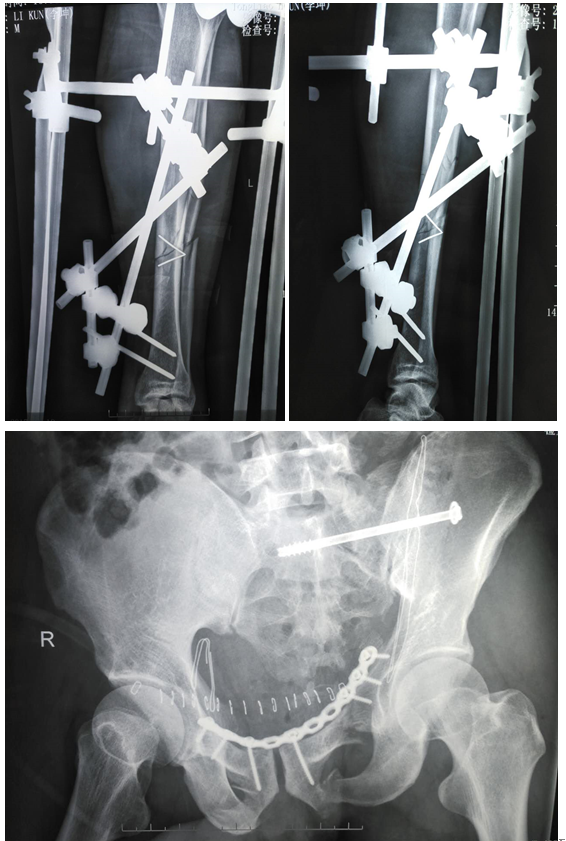

入院诊断:1、双侧耻骨上下支骨折;2、双侧坐骨支骨折;3、左骶骨骨折;4、左侧胫腓骨中下段开放性骨折;5、腰5椎体右侧横突骨折。刘利主任医师查看患者,阅片后指示:患者直接暴力损伤致骨盆前环损伤,左侧骶骨呈新月形骨折,伴有左侧坐骨神经损伤,左胫腓骨中下段呈开放性螺旋形骨折,需行手术治疗。入院当晚即行左胫骨中下段开放性骨折切开复位+外固定架固定术。术后切口无感染。左下肢行骨牵引,待患者病情平稳后于伤后第8天行双侧耻骨上支及左骶骨骨折切开复位内固定术,手术方法引用了当今流行的骶骨后路切开复位,C臂透视下闭合打入骶髂关节拉力螺钉固定骶骨骨折;以及改良Stoppa手术入路治疗骨盆前环损伤。手术进行顺利,病人病情平稳。

众所周知,骨盆骨折属于创伤骨科最为重要的部分之一,高能量骨盆损伤往往需要手术治疗,以挽救生命、防止骨盆不稳定或骨盆机型并发症的发生,其损伤大、死亡率高,复位困难等一直都是骨科医生棘手的问题。该患者如此高能量损伤实属罕见,在精心的术前准备及多次科内开展术前讨论的前提下,制定了该手术方案,优点:1、应用改良Stoppa手术入路不需切断腹直肌就可以有充分的手术视野去复位骨折。往往传统的手术入路在切断腹直肌后,术后患者会出现疼痛、切口下空虚,间隙形成,并有渗出,甚至感染;2、对两侧“死亡冠”区进行充分显露,结扎,避免术中及术后出血,危及生命,甚至死亡;3、利用后路小切口解决骶骨骨折的复位,并在透视下闭合打入骶髂关节拉力螺钉,减少了创伤出血,并达到了满意的稳定效果;4、一期行左胫骨开发性骨折切开复位外固定架固定术,顺应了当前应对开放性骨折的处理原则,不但减少了术后感染的风险,且同样有稳定效果;5、手术费用合理,减轻了患者的经济负担。该项技术填补我地区创伤骨科对骶髂关节螺钉固定技术及改良Stoppa手术入路治疗骨盆前环损伤的空白。?